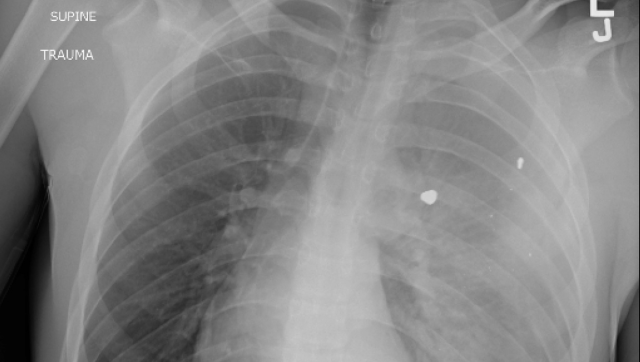

A doctor in US working in an emergency has issued a concerning alert about the primary reason for fatalities among youngsters and adolescents in the United States. Dr. Sam Ghali recently posted an X-ray image on X (previously known as Twitter) depicting the chest of a young boy afflicted by a condition that has now claimed the position of being the chief cause of demise for kids and teenagers in the US. Dr. Ghali posed a question to his followers: “Can you determine the diagnosis?” The image exposes the child’s chest, revealing what seems to be foreign objects lodged within the lungs. “Any guesses? Prayers? To give you a hint, it’s not the FLU, RSV, or COVID,” supplemented Dr. Ghali.

Many of the responses accurately guessed that the image portrayed a gunshot wound. A recent analysis of data from the US Centers for Disease Control (CDC), which was published last week, reiterated that gunshots persist as the predominant cause of death for children in the US during 2021. This research, unveiled in the journal of the American Academy of Pediatrics, brought to light that 4,752 youngsters and adolescents (spanning from newborns to 19-year-olds) lost their lives due to gunshot injuries in 2021. Among these cases, approximately 64% were classified as homicides, nearly 30% as suicides, and 3.5% stemmed from “unintentional injury”. These statistics signify a notable surge of 41.5% in the rate of firearm-related deaths in the pediatric population from 2018 to 2021. “The significant rise in firearm-related deaths among children in 2020 garnered widespread attention, with many speculating that the increase could be attributed to the onset of the 2019 coronavirus disease pandemic and the exacerbation of underlying causes,” elucidated the authors. “Remarkably, even though the initial pandemic-induced fears and anxieties have subsided, firearm-related fatalities continued to hold their position as the foremost cause of death for children and adolescents in 2021.” Up to this point in the current year, data amassed by the Gun Violence Archive indicates that no fewer than 1,187 children and teenagers (ranging from newborns to 17-year-olds) have fallen victim to shootings.